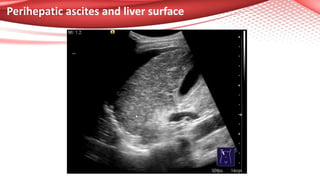

Perihepatic ascites and liver surface